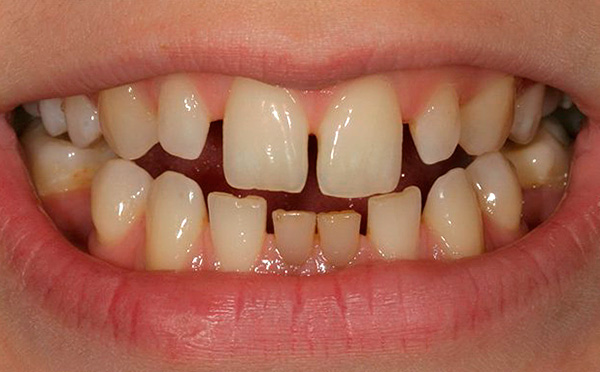

- com forte apinhamento dos dentes (quando não têm espaço suficiente na mandíbula, começam a crescer "aleatoriamente");

- em situações em que você vê que os dentes da criança ficam tortos;